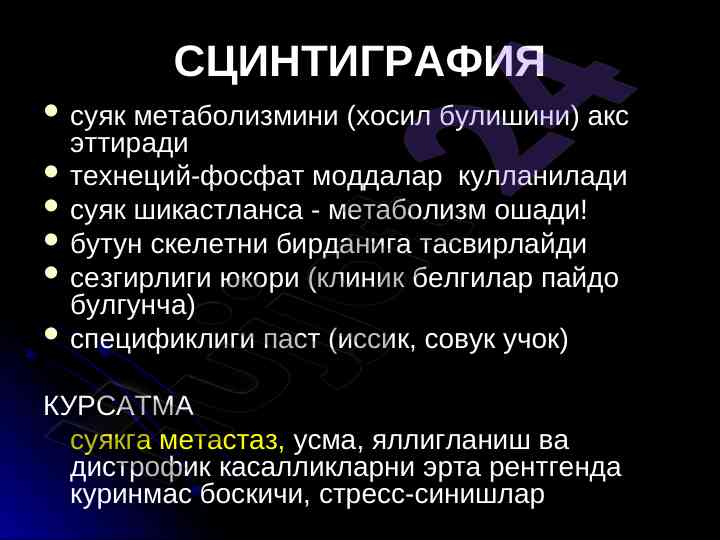

Рентгенография, ультрасонография ва сцинтиграфия усуллари тянч-харакат тизими касалликлари диагностикасида муhim аҳамиятга эга. Инсон организмининг юз бериши мумкин бўлган ўзгаришларни аниқлашда муҳим рол ўйнайди.